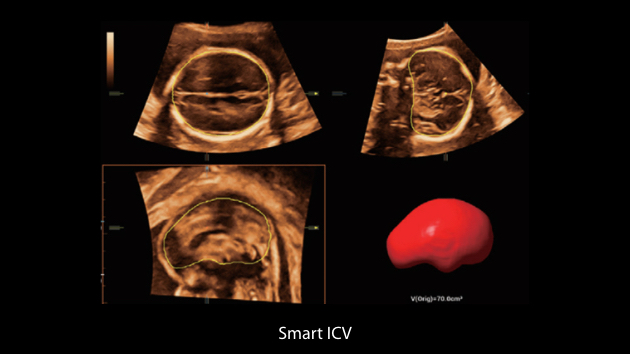

Obrazy kliniczne